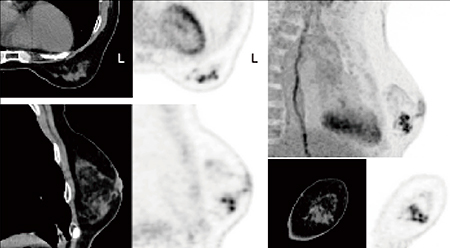

図1に症例を提示する。腹臥位で撮像することにより,乳房を伸展させ,胸郭の動きを抑制する。画像再構成はTOF+point spread function(PSF),880×880高分解能マトリックスの使用により,多発する小腫瘤を明瞭に描出している。

図1 左乳房BD領域に多発する小腫瘤の明瞭な描出

「伏臥位用乳房撮像クッションCPM」(中部メディカル社製)を使用し,腹臥位で撮像,TOF+PSF,880×880マトリックスの高分解能画像再構成を実施

(画像ご提供:九州大学病院様)